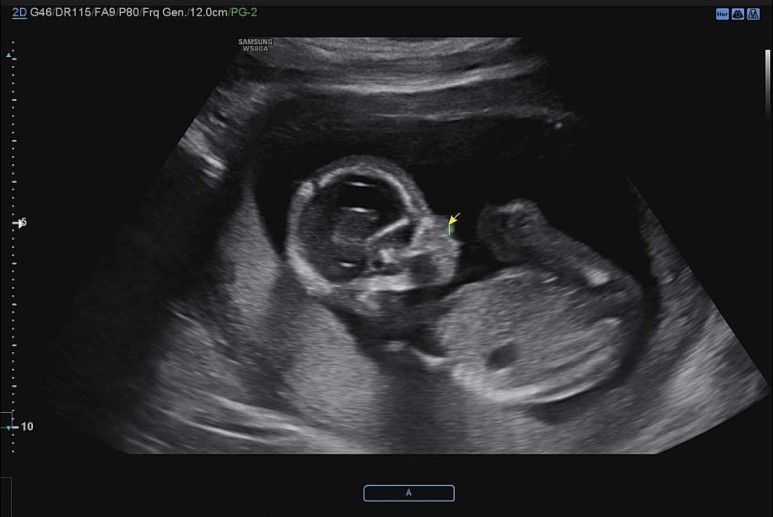

꿀잠이 오늘은 똑바로 앉아있기.

4주가 지나니 이제 척추뼈가 하나하나 다 보이고 머리도 훌쩍 커진게 눈에 보인다.

꿀잠이 오늘의 바이탈 144bpm!

쭉 뻗고 앉아있는 귀여운 ㅋㅋ 다리 ㅋㅋ

요기는 팔꿈치.

손을 머리쪽으로 올리고 있다.

이제 초음파 영상 구분하는 고수가 되어서 어디가 어딘지 척척.

콧대도 확인하고.

벌써 머리통이랑 콧날이 예쁜것 같아 내새꾸.

초음파 선생님이 엉덩이 사이를 열심히 들여다 보셨지만, 탯줄이 교묘하게 가리고 있어서 도저히 성별을 가늠할 수 없다고 하셨다. 그런데 내 느낌엔 슬쩍 슬쩍 지나가는 화면에 다리 사이에 아무것도 보이지 않는게 자꾸 포착되어서 딸인것 같은 느낌적인 느낌을 느꼈다..!